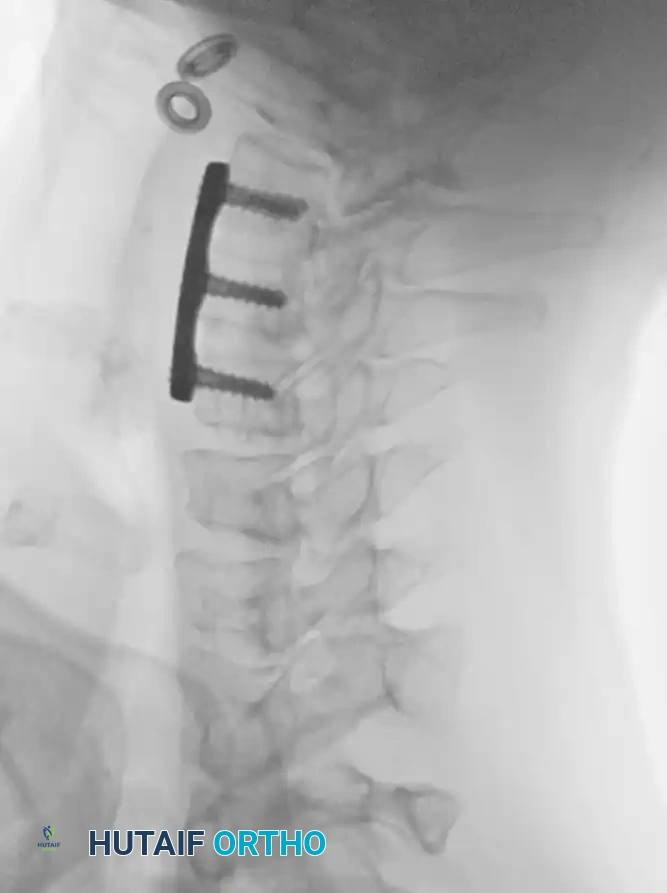

Anterior Plating Technique (Technique 35-16)

When anterior column reconstruction is required (e.g., post-corpectomy), anterior plating provides rigid stabilization.

- Measurement and Selection: Measure the distance between the middle of the cranial vertebra and the middle of the caudal vertebra to be included in the fixation. Use this caliper measurement to select the appropriate plate length.

- Contouring: If necessary, use a plate bender to conform the plate to the patient's specific spinal anatomy. Make several slight bends along the length of the plate and between the screw holes to obtain a consistent radius of curvature.

- Positioning: Using a plate holder, place the plate on the vertebral column in the optimal anatomical position.

- Temporary Fixation: Temporarily fix the plate with small pins screwed into the cortical wall. Insert these self-cutting pins diagonally through the screw holes to obtain sufficient provisional stability.

- Drilling: Place the drill guide on the plate. The guide limits pilot holes to the orientation of the integrated blocking ring (0 to ± 10 degrees sagittally and 6 degrees axially). Use the appropriate drill bit (10 mm, 12 mm, 14 mm, 16 mm, or 18 mm) to prepare the pilot hole.

- Screw Insertion: While tapping is an option, modern screws are typically self-tapping. Insert the 4.0-mm or 4.5-mm screws into the pilot holes. Tighten until locked into the plate, ensuring the locking mechanism (washer) fully covers the screw head.

- Graft Securing: If a corpectomy and structural grafting were performed, secure the graft to the plate using standard 4-mm screws placed in the intermediary screw holes.

- Closure: Thoroughly irrigate the wound and close in layers over a subfascial drain.

Associated Surgical & Radiographic Imaging